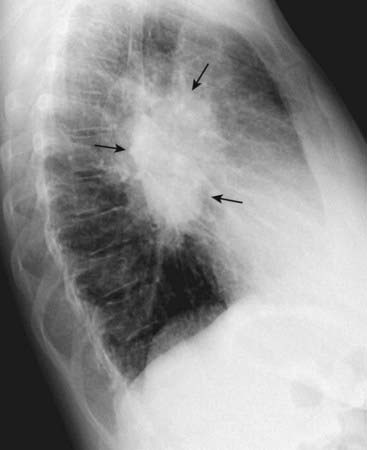

image

Figure 2-6 Hilar mass on lateral radiograph.

Left lateral view of the chest shows a discrete lobulated mass in the region of the hila (solid black arrows). Normally, the hila do not cast a shadow that is easily detectable on the lateral projection. This patient had bilateral hilar adenopathy from sarcoidosis but any cause of hilar adenopathy or a primary tumor in the hilum would have a similar appearance.